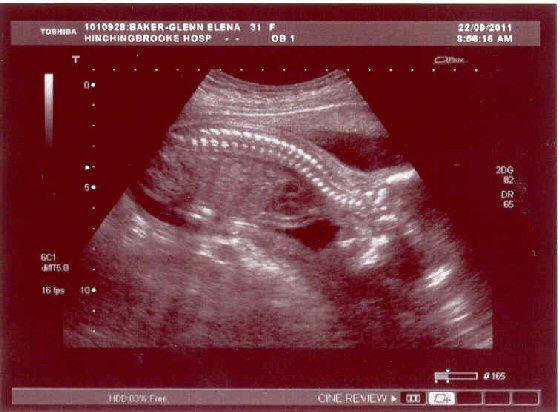

These are the photos taken on 22/09/11: